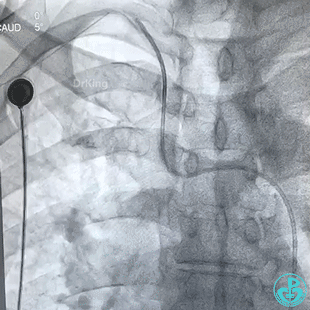

桡动脉鞘进JR 4.0指引导管,送入Sion,沿Sion送入2.5mm球囊,球囊越过穿刺导丝到达远端,6atm“打起来”后回撤,导丝被球囊带回来到指引导管口附近。

持续球囊锚定导丝调整指引导管角度,对准后回拉球囊,将导丝带入指引导管内,最后连同指引导管一起成功拉出。